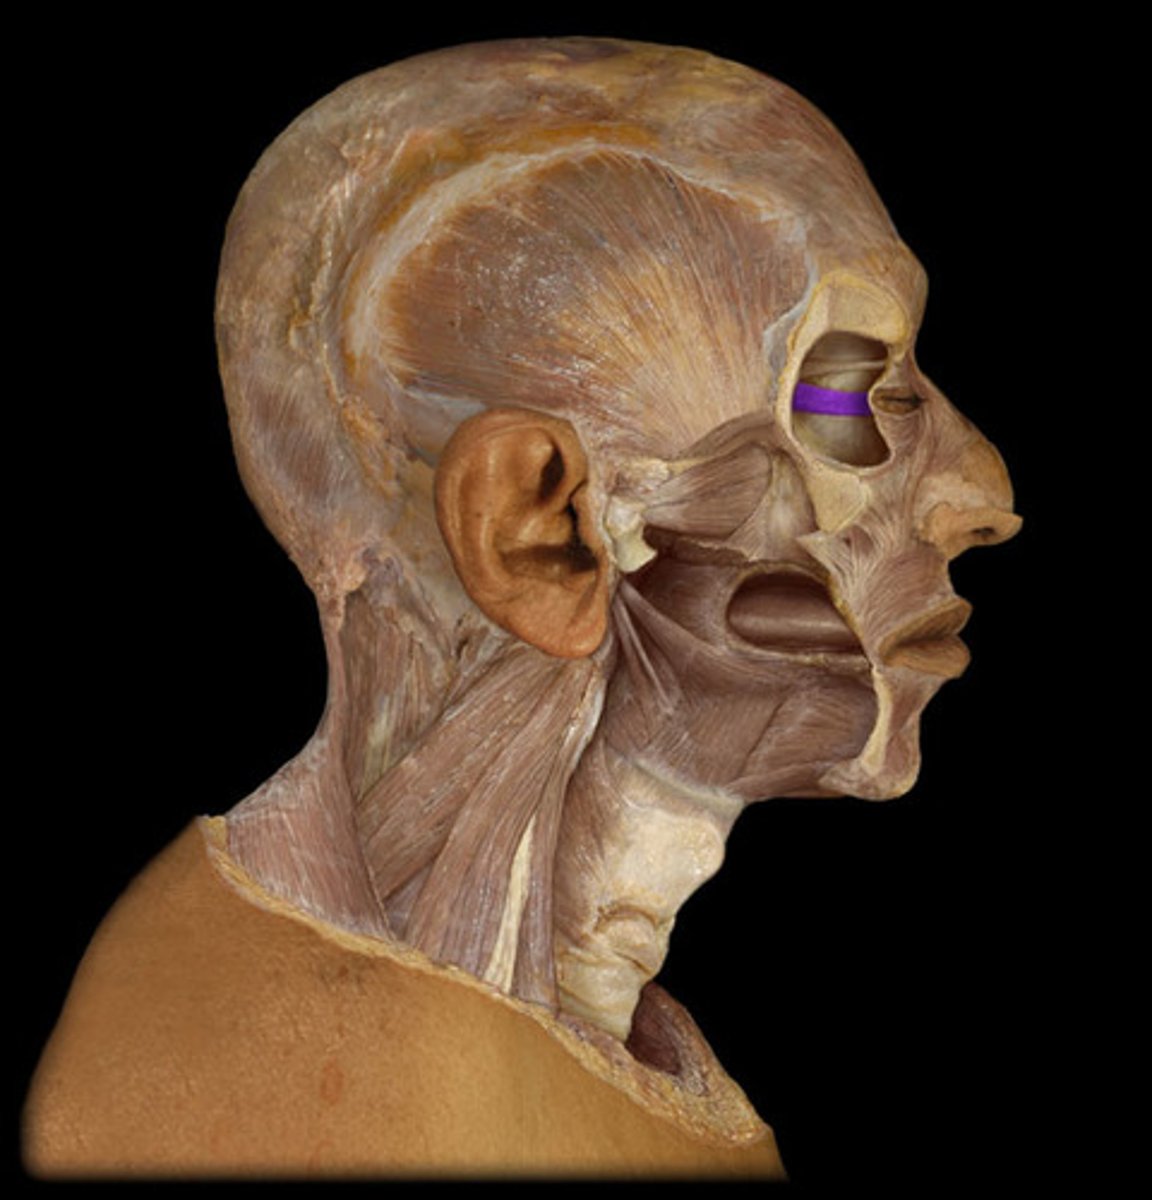

Orbicularis oculi

Levator palpebrae superioris